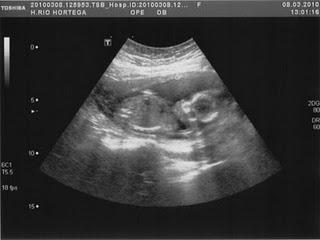

A mediados de febrero, pude retomar la medicación.El 1 de marzo fue el día que me hicieron la amnio. Qué duro fue, me pasé la prueba llorando, aterrada. El día 10 supimos que el feto no tenía la enfermedad genética que temíamos. El 19, se decartó el síndrome de down y otras anomalías cromosómicas, se nos comunicó que era una niña sana- Ese fue el día en que hicimos público el embarazo, así presentamos a nuestra muñeca: